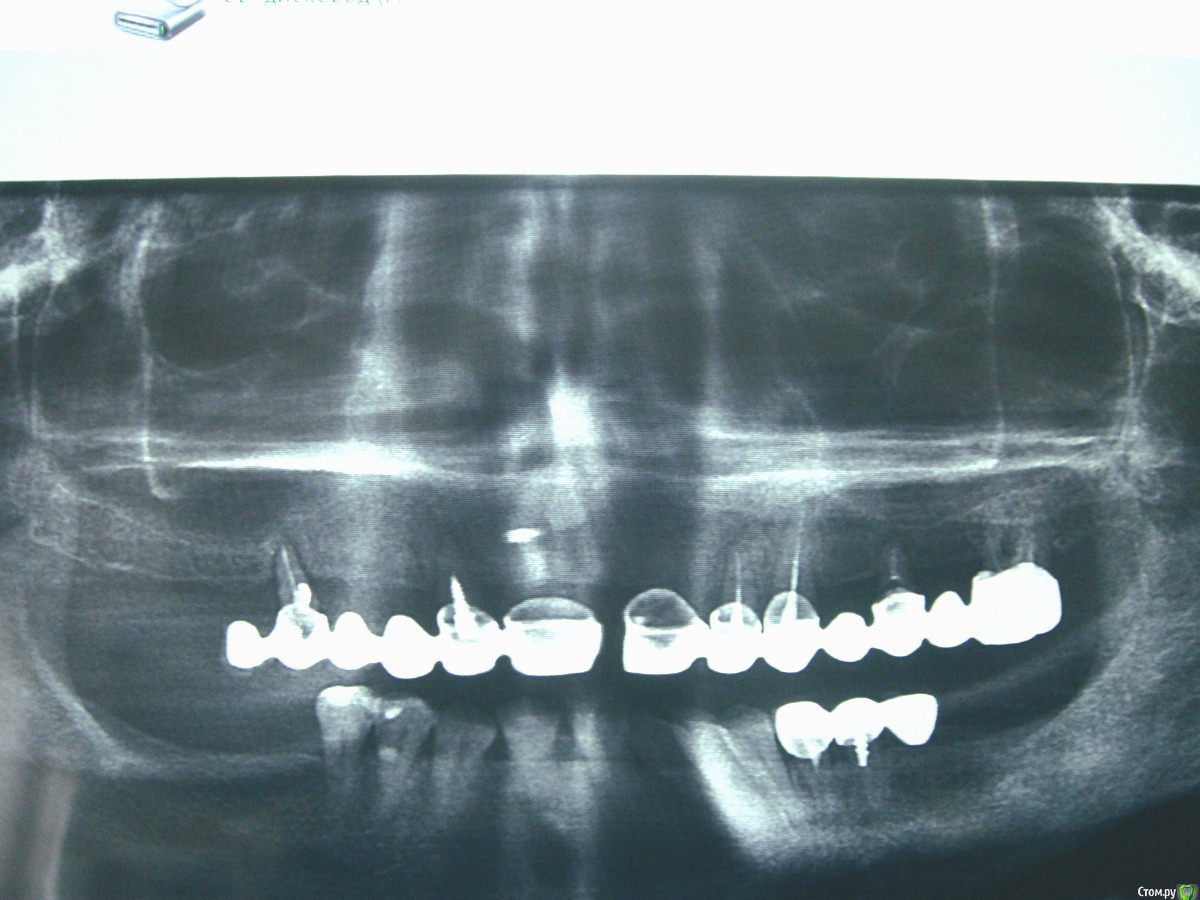

dr.Dre Опубликовано 25 ноября, 2015 Поделиться Опубликовано 25 ноября, 2015 Добрый вечер пациентка 47 лет,мостик справа 2 степень подвижности,от имплантации пациентка отказалась,какую конструкцию здесь сделать. Ссылка на комментарий

DR.P Опубликовано 25 ноября, 2015 Поделиться Опубликовано 25 ноября, 2015 (изменено) Добрый вечер! Снимок не информативный, нужно лучше качество. Но тут нужно все делать комплексно и верх и низ и право и лево)Комбинация несъемного со съемным протезированием. Снимать все, санировать (что необходимо удалить, что возможно сохранить) и только потом уже будет видна будущая конструкция.Верх скорее всего полный съемный. Изменено 25 ноября, 2015 пользователем DR.P Ссылка на комментарий

anvladd Опубликовано 25 ноября, 2015 Поделиться Опубликовано 25 ноября, 2015 (изменено) Все на верху на удаление. +100 полный съемный верх,част. съемн низ. Изменено 25 ноября, 2015 пользователем anvladd Ссылка на комментарий

Карен Аванесов Опубликовано 25 ноября, 2015 Поделиться Опубликовано 25 ноября, 2015 Полный съемный вверх, частично съемный вниз. 3 Ссылка на комментарий